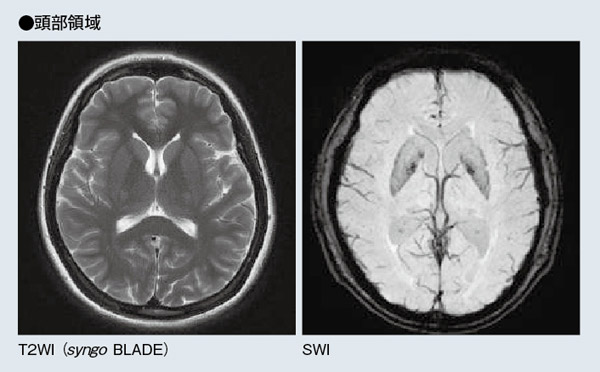

同クリニックではいまのところ,頭頸部領域と整形領域の撮像が約8割を占めている。頭頸部領域では,出血を疑う症例や外傷以外は基本的にMRIがファーストチョイスとなり,症例は脳梗塞や脳動脈瘤,一過性脳虚血発作(TIA)などが多い。MAGNETOM Avanto1台体制では,アキシャルのT2強調像,T2 FLAIR,T1強調像,拡散強調画像(DWI)を基本としていたが,MAGNETOM ESSENZAは検査スループットが高いため,同じ撮像時間でT2*強調像のほか,必要に応じてSWIまで追加できるようになった。また,整形領域では,腰椎椎間板ヘルニアや脊柱管狭窄症,半月板損傷,靭帯損傷などの撮像が多く行われている。腰椎では,T2強調像,T1強調像が2方向ずつに加えて,MRミエログラフィが追加された。このほか,腹部領域では,胆石の術前MRCP,T2強調像,T1強調像,DWIに加えて,3DのT1強調ダイナミックMRIであるsyngo VIBEを撮像している。息止め下約20秒で三次元画像が得られ,病変部の細かい部分まで容易に観察できるため,有用性が高いという。

体動のある症例でも,syngo BLADEを用いることにより,ルーチン検査として十分な検査が行える。

ルーチン検査には用いていないが,syngo SWIにおいても静脈の描出は良好である。